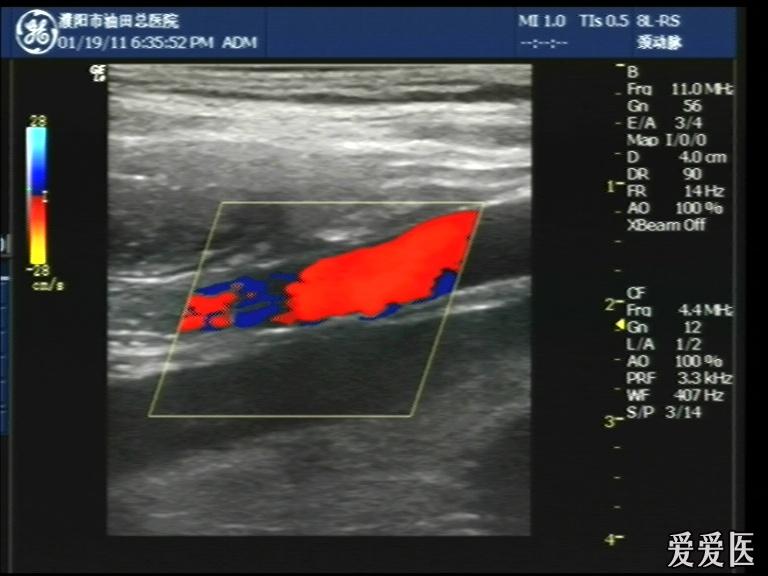

超声检查:于下腹部可见“双环征象”,双环重叠长约6mm,检查期间观察可见肠蠕动;CDFI:未见明显异常血流信号。

超声提示:下腹部双环征,考虑肠套叠可能,请结合临床